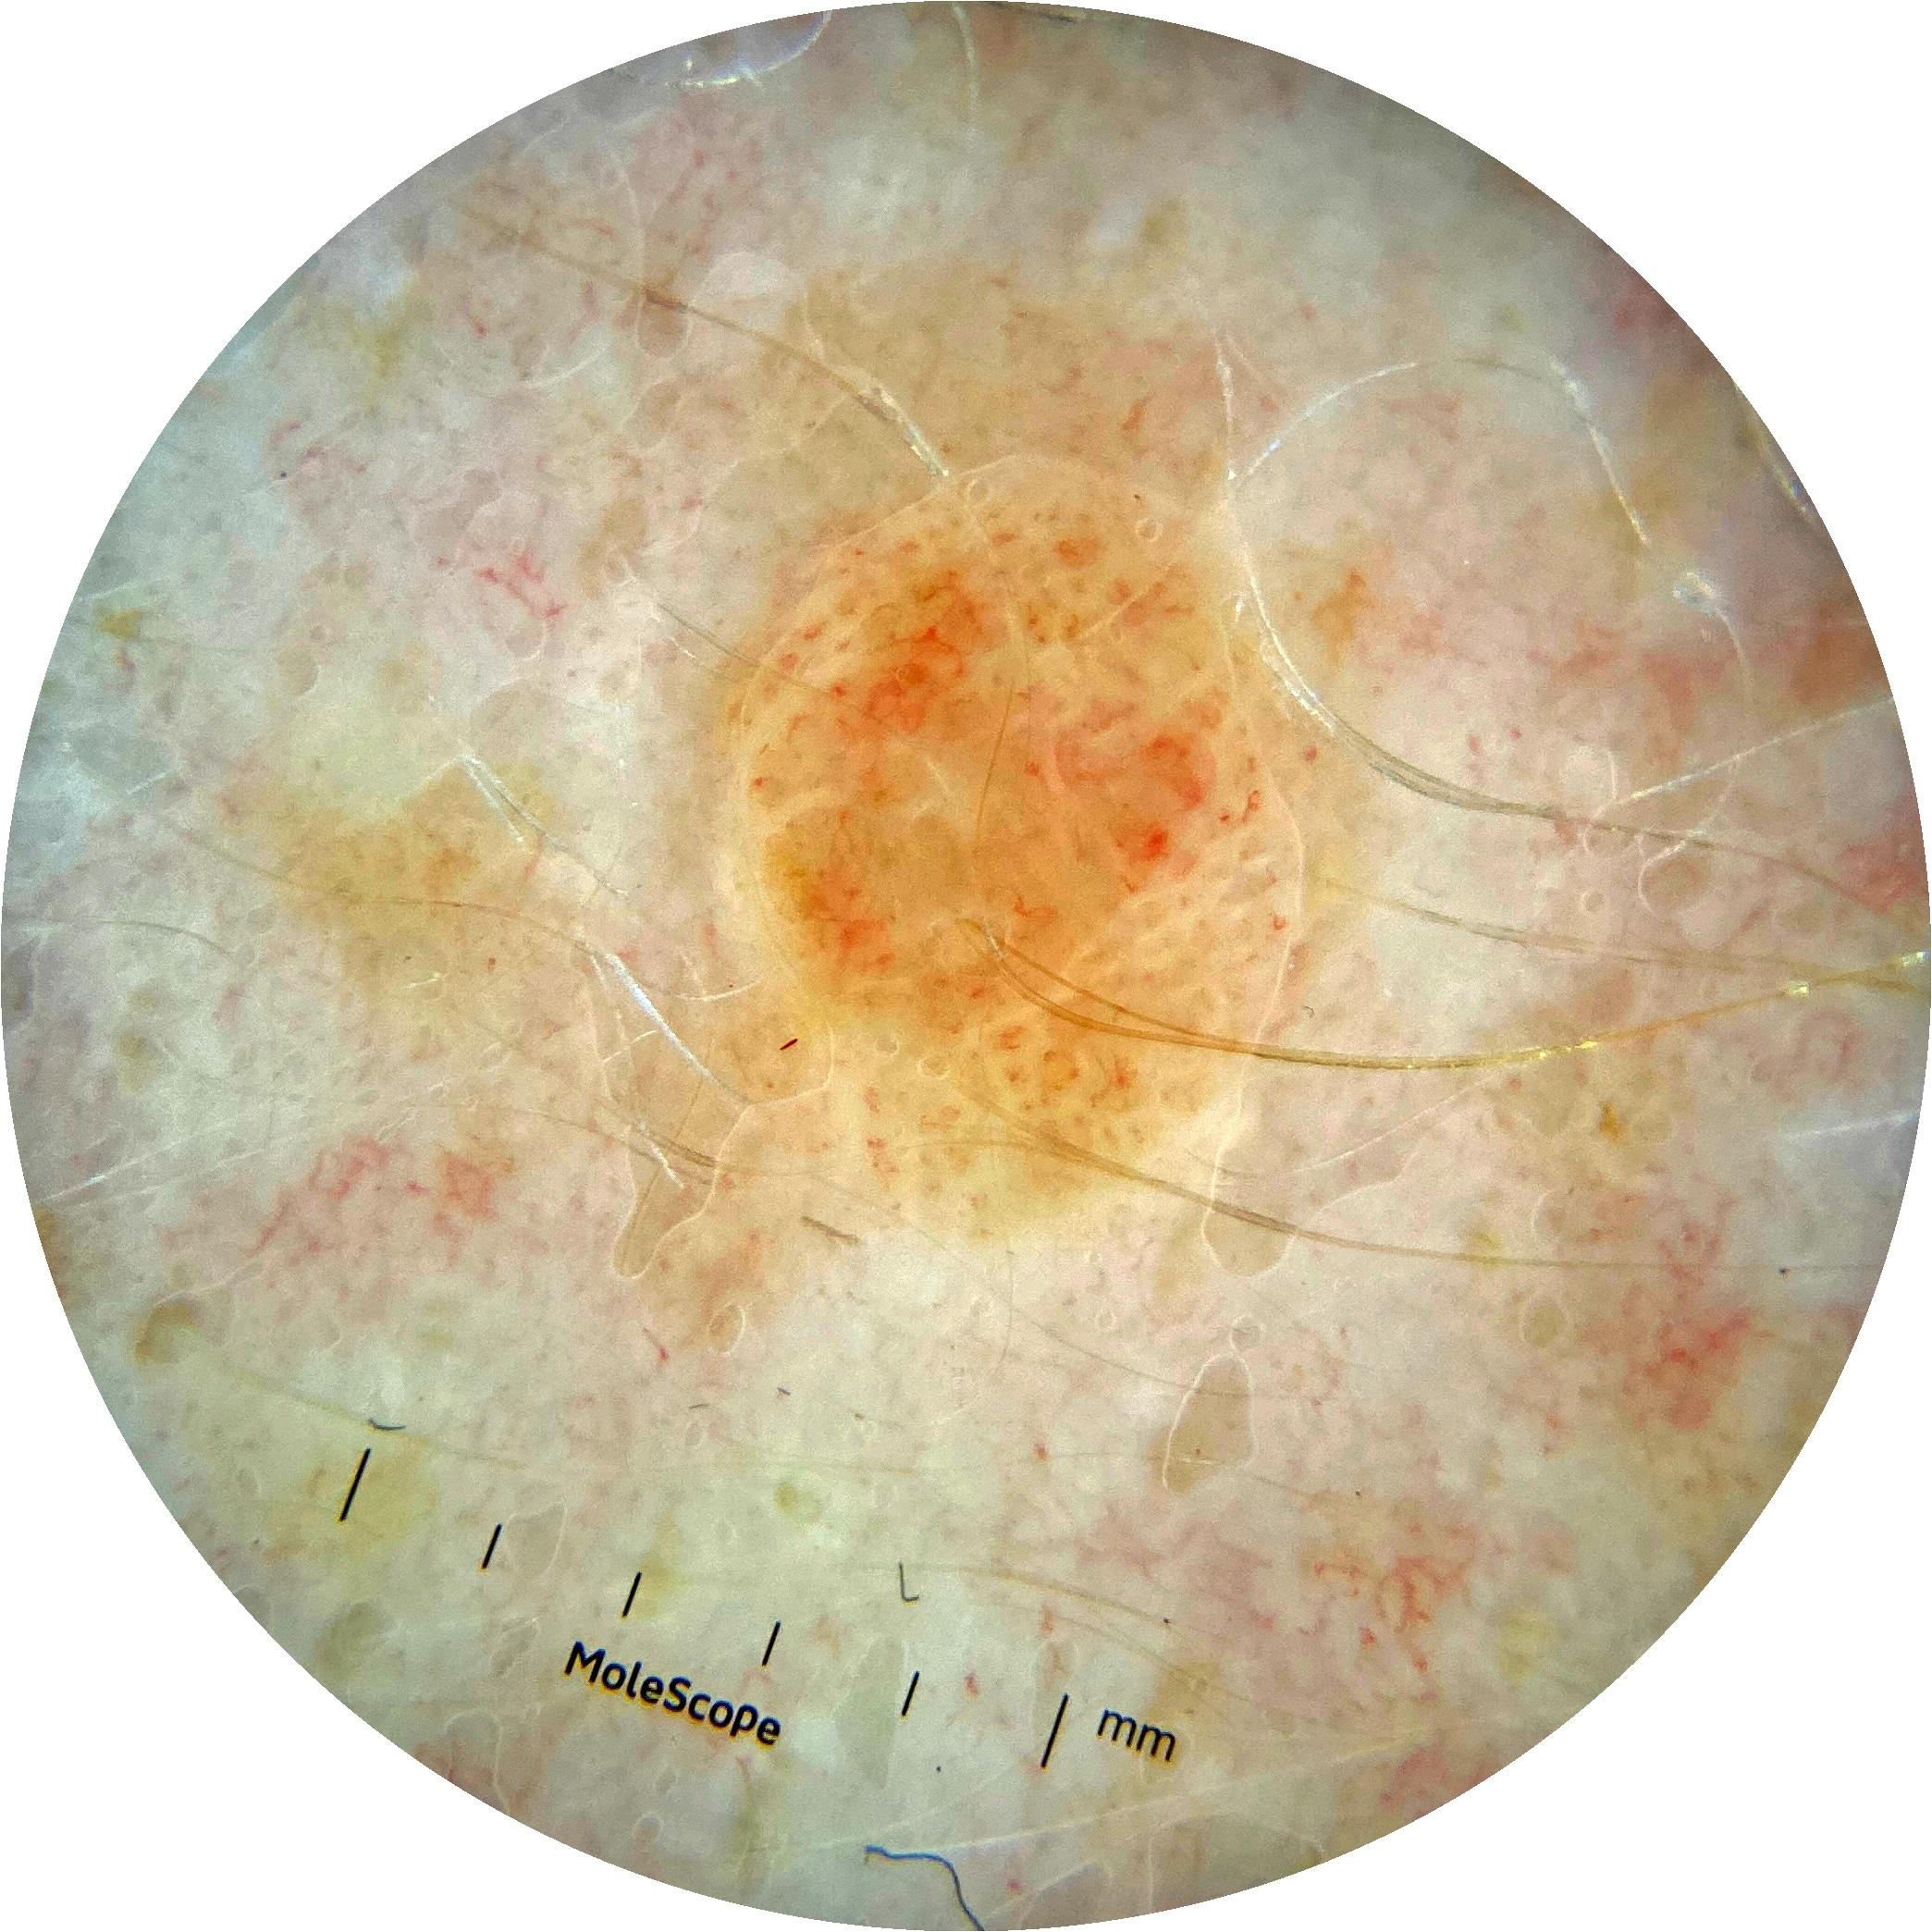

ISIC_3176953

2135 x 2135

diagnosis_1 Malignant

diagnosis_2 Malignant adnexal epithelial proliferations - Follicular

diagnosis_3 Basal cell carcinoma

image_type dermoscopic